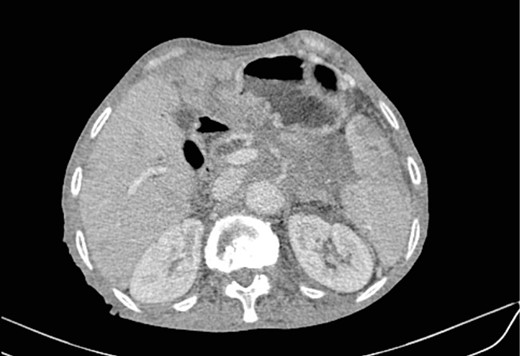

Mr. A. is a 65-year-old hypertensive patient presenting with acute epigastric pain associated with abdominal bloating. Biological settings showed amylasemia at 450 IU/L and lipasemia at 525 IU/L. Abdominal CT scan revealed heterogenous poorly defined mass in the pancreatic head with low enhancement (Figs 1 and 2). The CA 19–9 assay was 280 IU/L. Cephalic duodenopancreatectomy was performed. Histological examination of the operative specimen revealed a solid, trabecular, undifferentiated carcinomatous process (Fig. 3) expressing markers (CK(AE1-AE3) and p40) (Fig. 4), confirming the diagnosis of primary squamous cell carcinoma of the pancreas. The extension study showed no secondary localization.

Low-enhancing poorly defined mass in the pancreatic head with surrounding fat stranding (arrow).

Parenchymal atrophic changes and main pancreatic duct dilatation distal to the mass (blue arrow). Extra and intrahepatic bile ducts are dilated (red arrow).